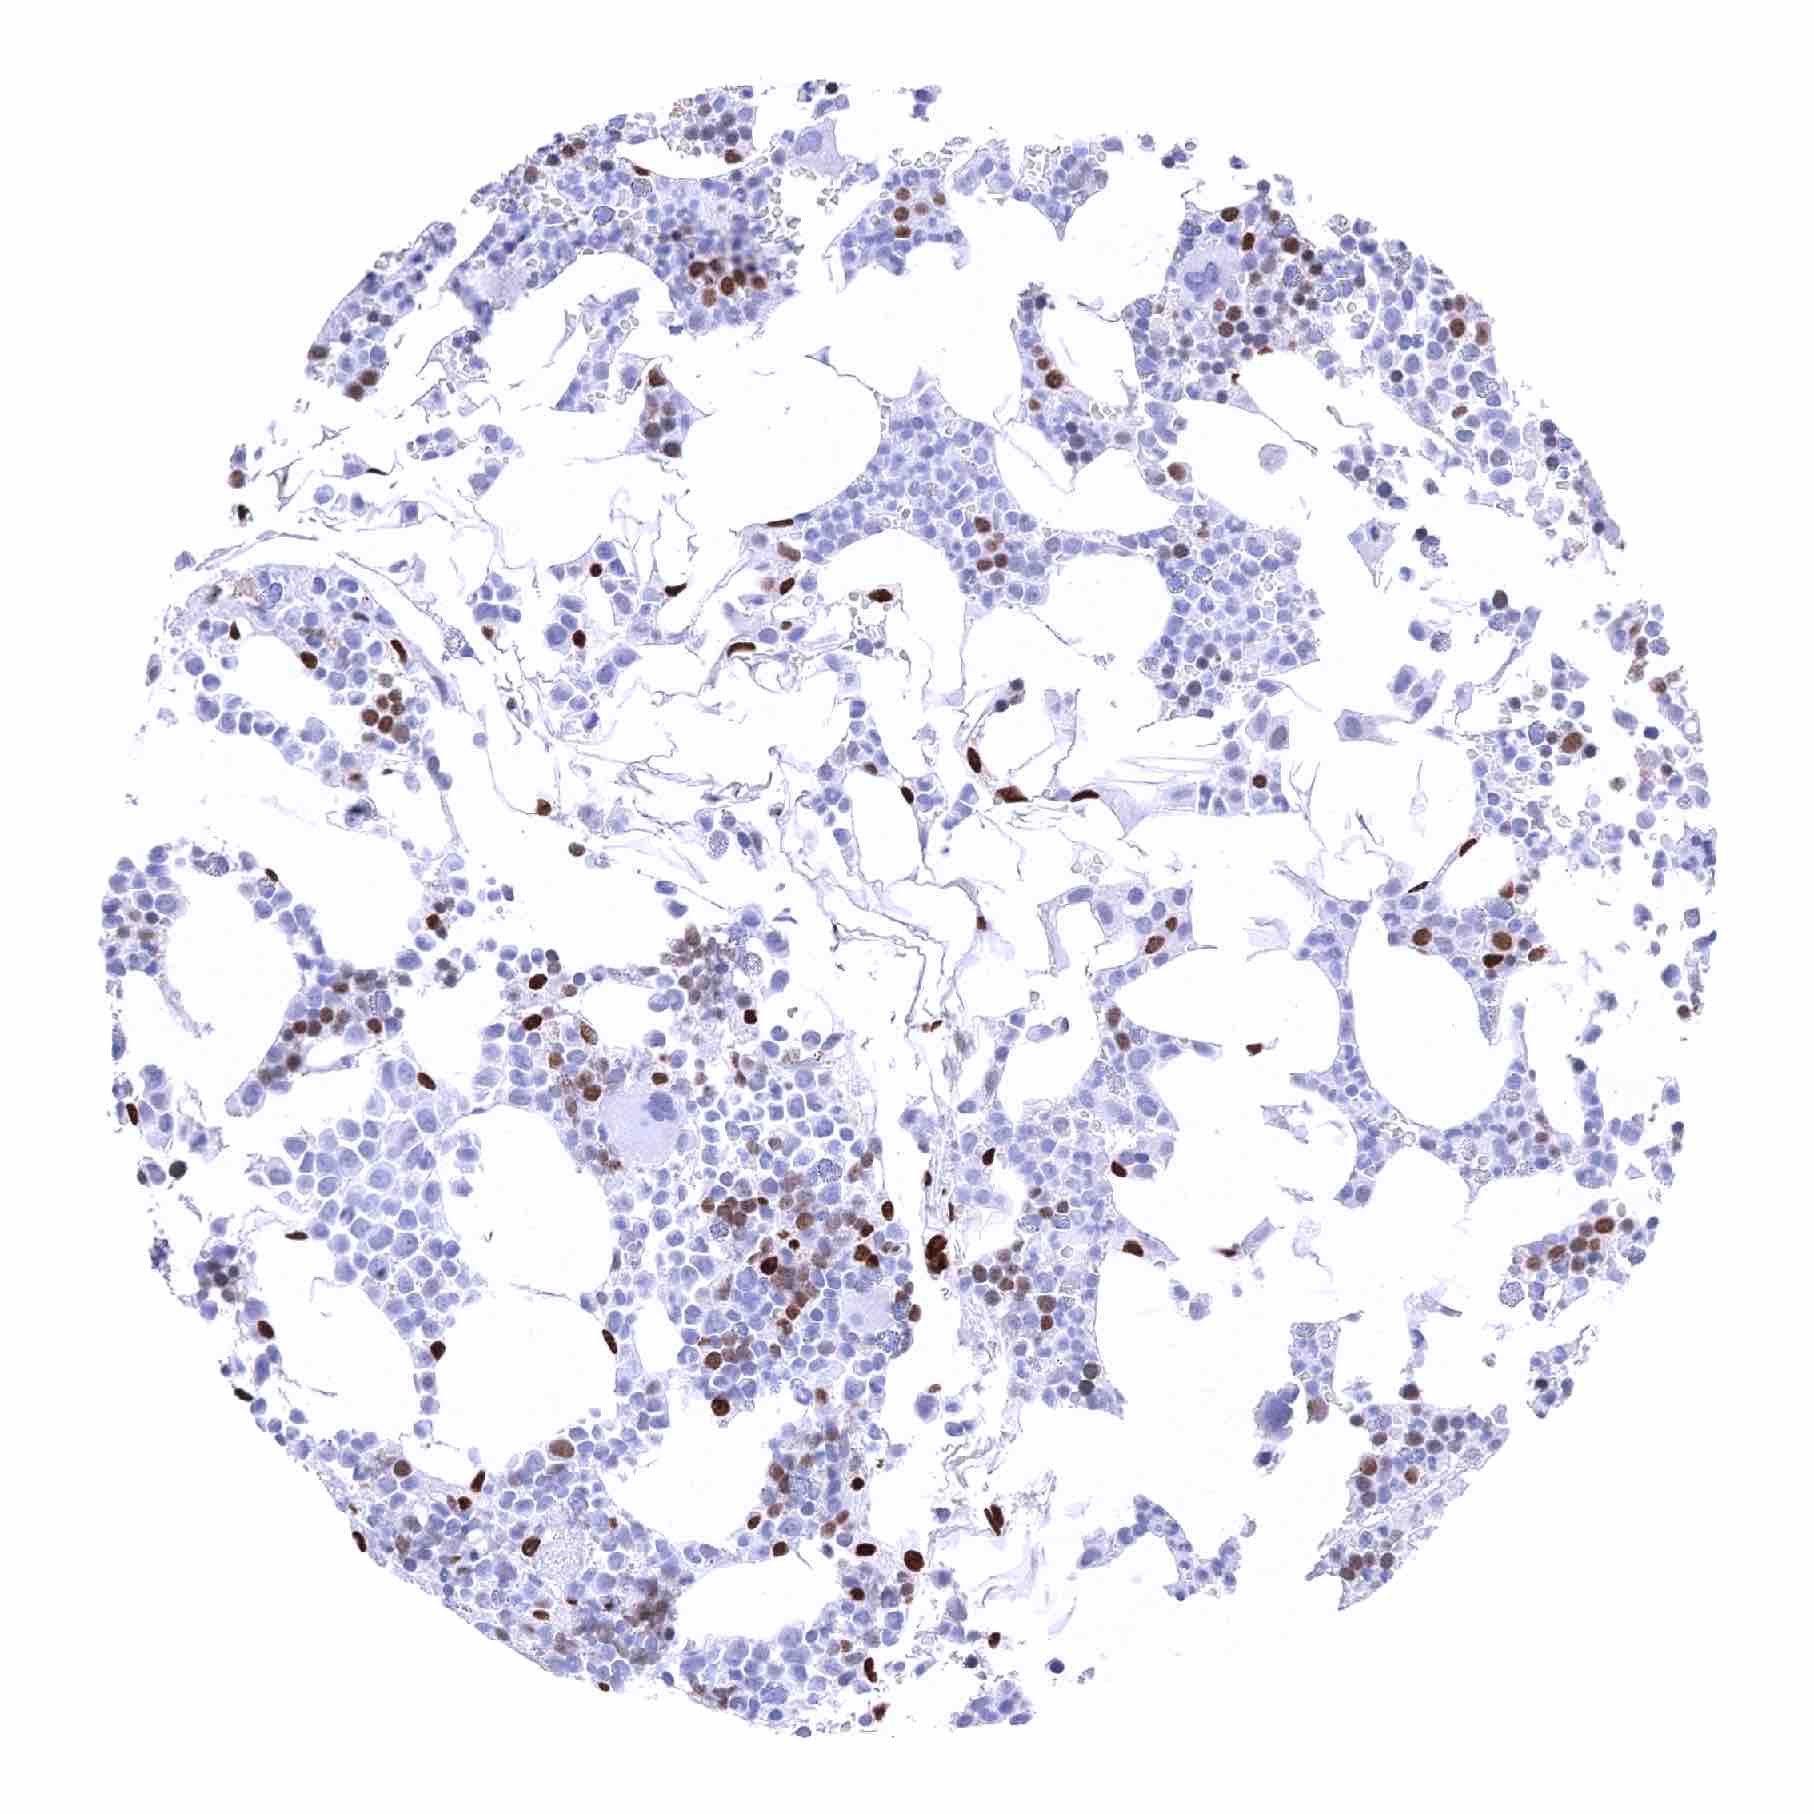

| Urinary bladder, urothelium – Distinct nuclear NFIX staining of urothelial cells although there is a significant decrease of NFIX staining intensity from the basal to the superficial cell layers. Umbrella cells are largely NFIX negative |